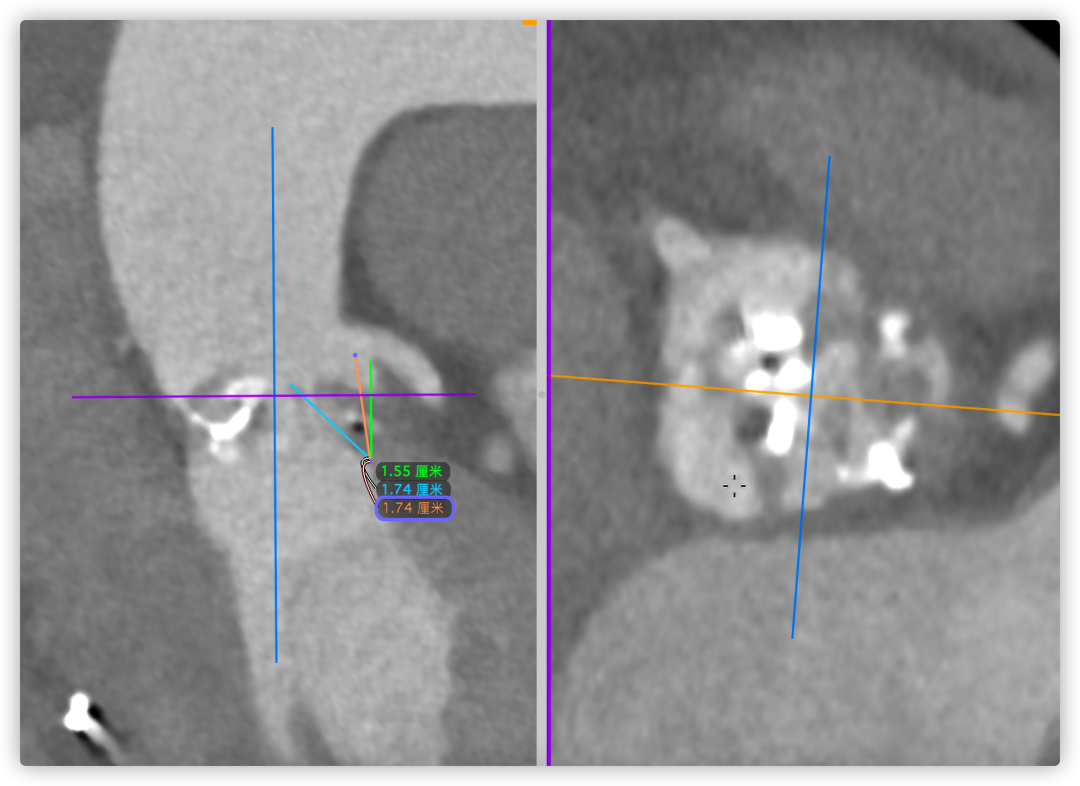

根部角度/瓣环/左室流出道

左冠风险评估

间隔膜部

26VenusAplus+snare